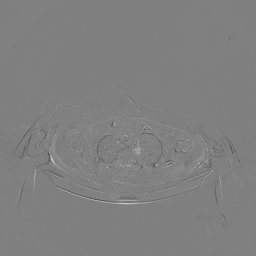

III-C Uncertainty analysis

Classical diffusion models reconstruct images by progressively denoising from an initial Gaussian noise image, a process that inherently introduces uncertainty due to random noise initialization. In contrast, I2SB directly learns a diffusion bridge between two sample distributions, effectively bypassing the need for random noise sampling and thereby reducing reconstruction variability.

To assess the uncertainty of our method, we performed multiple reconstructions using different random seeds. As shown in Fig. 3, the ground truth and representative sampled images are presented in Fig. 3(a) and (b–d), respectively. The mean reconstruction and pixel-wise standard deviation across runs are displayed in Fig. 3(e) and (f). Only minimal differences are observed between reconstructions, indicating that I2SB produces highly consistent results. These findings confirm that, compared with classical diffusion models, I2SB substantially reduces uncertainty across repeated reconstructions.